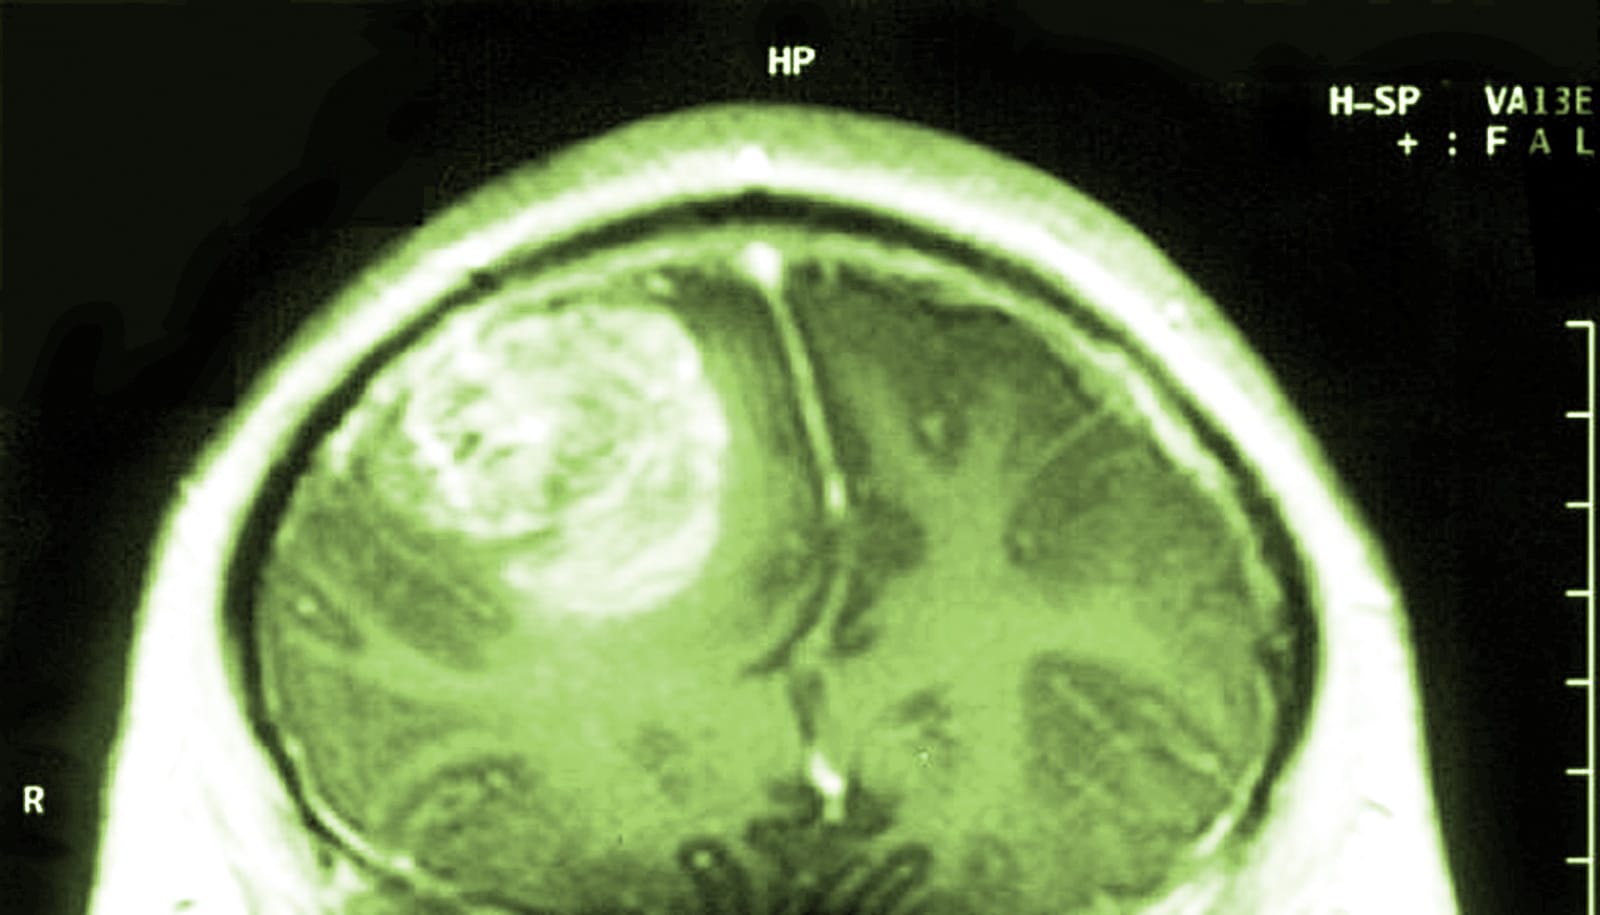

Highgrade tumor (glioblastoma) after radiation therapy. The Can Radiation Cure Glioblastoma Radiation therapy is often a critical component of glioblastoma treatment. Over the past several decades,. Conventional radiotherapy with photons, along with concurrent and adjuvant temozolomide, is the mainstay for treatment of gbm although no. Whether and how radiation therapy should be applied depends on. Radiation therapy can shrink or kill tumor cells. The standard of care for glioblastoma is the. Can Radiation Cure Glioblastoma.